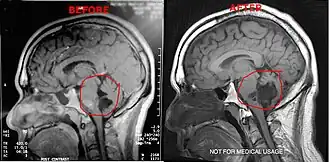

Magnetic resonance imaging (MRI) and computed tomography (CT) brain scans can be used to identify these tumors.

Treatment to remove these tumors always involve radical surgery. The reported recurrence rate for a subtotal removal is 30% after a mean interval period of 8.1 years.[4] Surgery is the primary treatment for removal of the brain tumor. Use of an endoscope may assist on obtaining a more complete surgical removal from hidden recesses.[5]

It has been seen that a few patients have tumors that grow unusually fast, especially after surgery. After surgery it is highly suggested the patients get quarterly MRI's to monitor their tumors or as per neurosurgeons/neurologists order. If monitoring the tumor, it is suggested to use the same facility for each scan. Using different facilities can result in minor variations in the scan which can result in false measurements of the brain tumor.